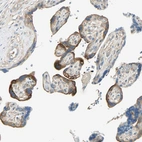

Immunohistochemical staining of human testis shows moderate cytoplasmic positivity in cells in seminiferous ducts.